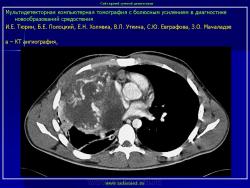

Средостение.  "Опухолевый рост".